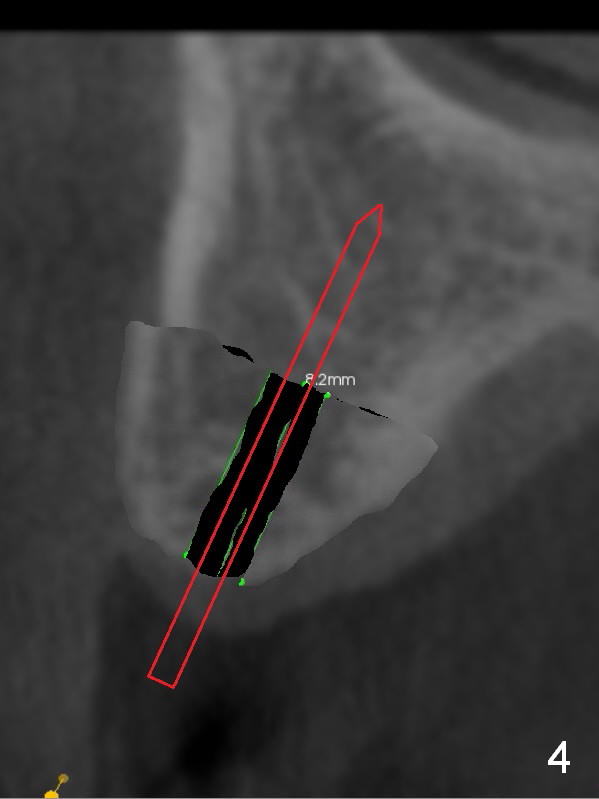

The fearful patient is satisfied with implant placement at #29 and will return to have #5 implant placed. Fig.1 is coronal section of the site of #5 (B: buccal). It shows the narrow crest and low bone density (40-200 Hounsfield unit). Start bone expansion with #15 blade slightly palatal (Fig.2 green line), followed by bone scalpels and bone blades. The latter leads to differential expansion of the buccal and palatal plates (Fig.3 arrows). Once the crestal bone is expanded, use drills or osteotomes (RTs) for deeper portion of osteotomy (Fig.4 red arrow). Finally an appropriately-sized implant is placed (Fig.5). Also prepare bone expanders. Upper Arch Reconstruction, Upper Premolar Immediate Implant Xin Wei, DDS, PhD, MS 1st edition 04/08/2016, last revision 06/12/2019